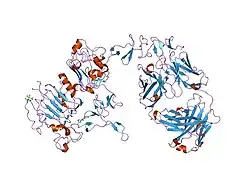

The ErbB family consists of four individual plasma membrane-bound receptor tyrosine kinases. One of which is erbB-2, and the other members being erbB-1, erbB-3 (neuregulin-binding; lacks kinase domain), and erbB-4. All four contain an extracellular ligand binding domain, a transmembrane domain, and an intracellular domain that can interact with a multitude of signaling molecules and exhibit both ligand-dependent and ligand-independent activity. Notably, no ligands for HER2 have yet been identified.[13][14] HER2 can heterodimerise with any of the other three receptors and is considered to be the preferred dimerisation partner of the other ErbB receptors.[15]

Dimerisation results in the autophosphorylation of tyrosine residues within the cytoplasmic domain of the receptors and initiates a variety of signaling pathways.